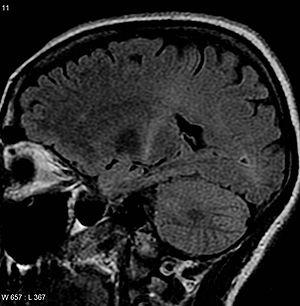

MRI (axial FLAIR) demonstrates increased T2 signal within the posterior part of the internal capsule, consistent with the diagnosis of ALS.

No test can provide a definite diagnosis of ALS, although the presence of upper and lower motor neuron signs in a single limb is strongly suggestive.[2] Instead, the diagnosis of ALS is primarily based on the symptoms and signs the physician observes in the person and a series of tests to rule out other diseases.[2] Physicians obtain the person's full medical history and usually conduct a neurologic examination at regular intervals to assess whether symptoms such as muscle weakness, atrophy of muscles, hyperreflexia, and spasticity are worsening.[2] A number of biomarkers are being studied for the condition, but so far are not in general medical use.[89][90]